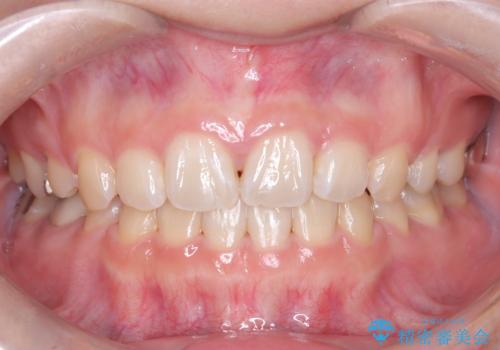

前歯の突出を防ぎながらガタつきを解消。上下左右4番抜歯による審美ワイヤー矯正

担当医 河口智英